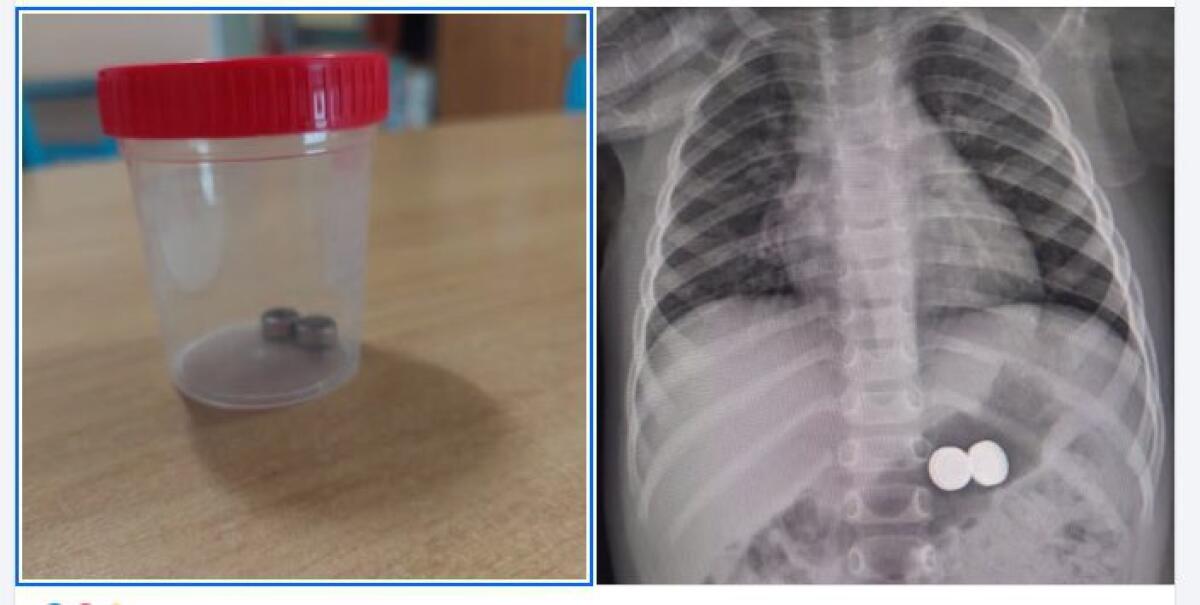

Una bambina di un anno è stata condotta d’urgenza all’ospedale Garibaldi-Nesima, dopo aver ingerito due batterie a bottone. Il pronto intervento dei medici ha permesso di rimuovere i corpi estranei senza conseguenze gravi.

L’incidente è stato segnalato dai genitori della piccola, che hanno prontamente trasportato la bambina all’ospedale di Acireale. A seguito della segnalazione, è stato immediatamente contattato il Pronto Soccorso Pediatrico del presidio ospedaliero Garibaldi-Nesima, dove la dott.ssa Rita Leocata e la dott.ssa Valeria Di Stefano hanno immediatamente dato disponibilità per accogliere la piccola e procedere alla rimozione delle batterie.

Una volta arrivata al Pronto Soccorso Pediatrico, è stato prontamente allertato il gastroenterologo, dott. Domenico Catarella, insieme agli anestesisti della sala operatoria, dott. Giuseppe Calabrese e dott.ssa Lucia Terranova. Grazie alla loro tempestiva collaborazione, si è proceduto con successo alla sedazione e rimozione dei corpi estranei.